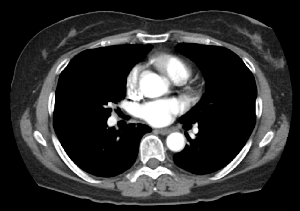

CT는 몸의 단면을 영상화하여 각종 질환을 진단하는 영상의학과 장비 중 하나입니다.

의료용 방사선을 이용하는 X-ray 검사와 비교할 때 인체의 해부학적 구조물이 겹쳐져 보이지 않고 인체의 축상면을 영상으로 획득합니다.

획득된 영상을 전산화된 프로그램을 이용하여 3차원(3D) 영상으로 재구성이 용이하며 인체의 시상면, 관상면 재구성도 가능합니다.

기존 X-ray검사에서는 진단이 불가능했던 질환을 더 자세하게 진단이 가능하게 하는 장비입니다.